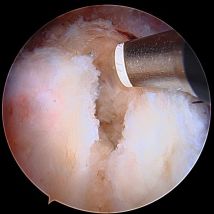

Hip arthroscopy, also referred to as "keyhole" or minimally invasive hip surgery, is typically necessary for hip pain that does not improve with conservative treatment. Small incisions are made only big enough to place a small video camera and specialized instruments into the hip joint, trochanteric space, and/or ischial space to clearly diagnose and treat hip pathology.

- Hip Labral Tear

Click on a hip condition below to see the repair.